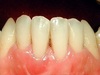

Cas 1

Un brossage excessif sur des gencives de faible épaisseur est souvent la cause des dénudations radiculaires traumatiques.